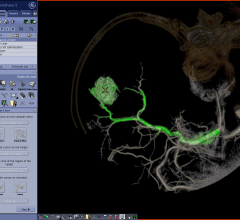

Fovia Medical Inc. and Contrast Imaging have collaborated to make natively integrated high definition volume rendering (HDVR) available throughout Contrast Imaging’s entire digital offering. With Fovia’s flexible and scalable advanced visualization HDVR software, Contrast Imaging can further streamline its fast, stable and integrated workflows at imaging centers throughout Australia.